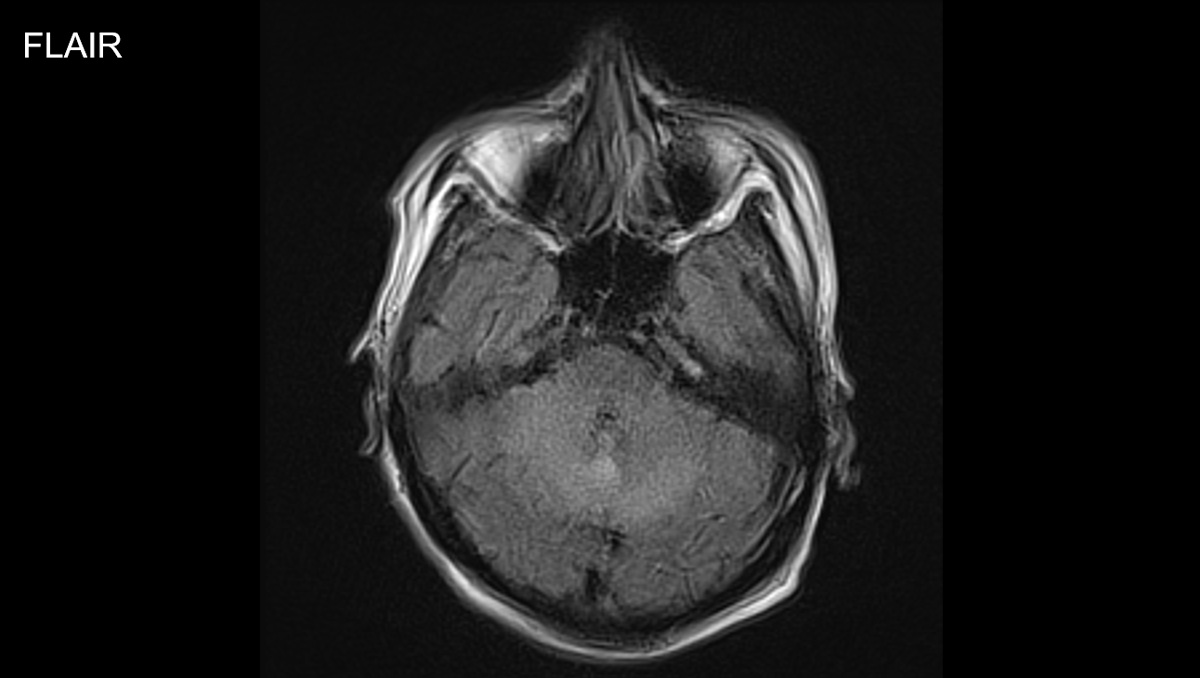

症例1:28歳男性

- 体動困難、呂律不良

- 4か月ほど前から歩行時の息切れあり、1か月前から下肢の疼痛が出現、1週間前からはベッド上で生活していた。

- 3日前から呂律が緩慢となり、増悪したため、父親が救急要請。